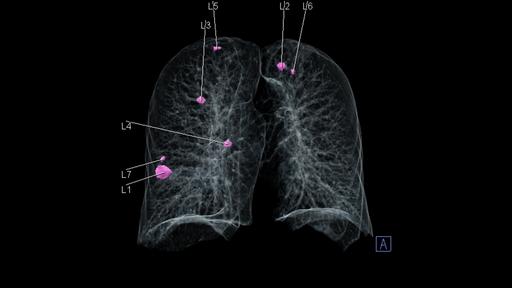

Explore our portfolio of ultra-low-dose CT scanners and AI tools that support you in your diagnostic assessments of lung cancer nodules during screening.